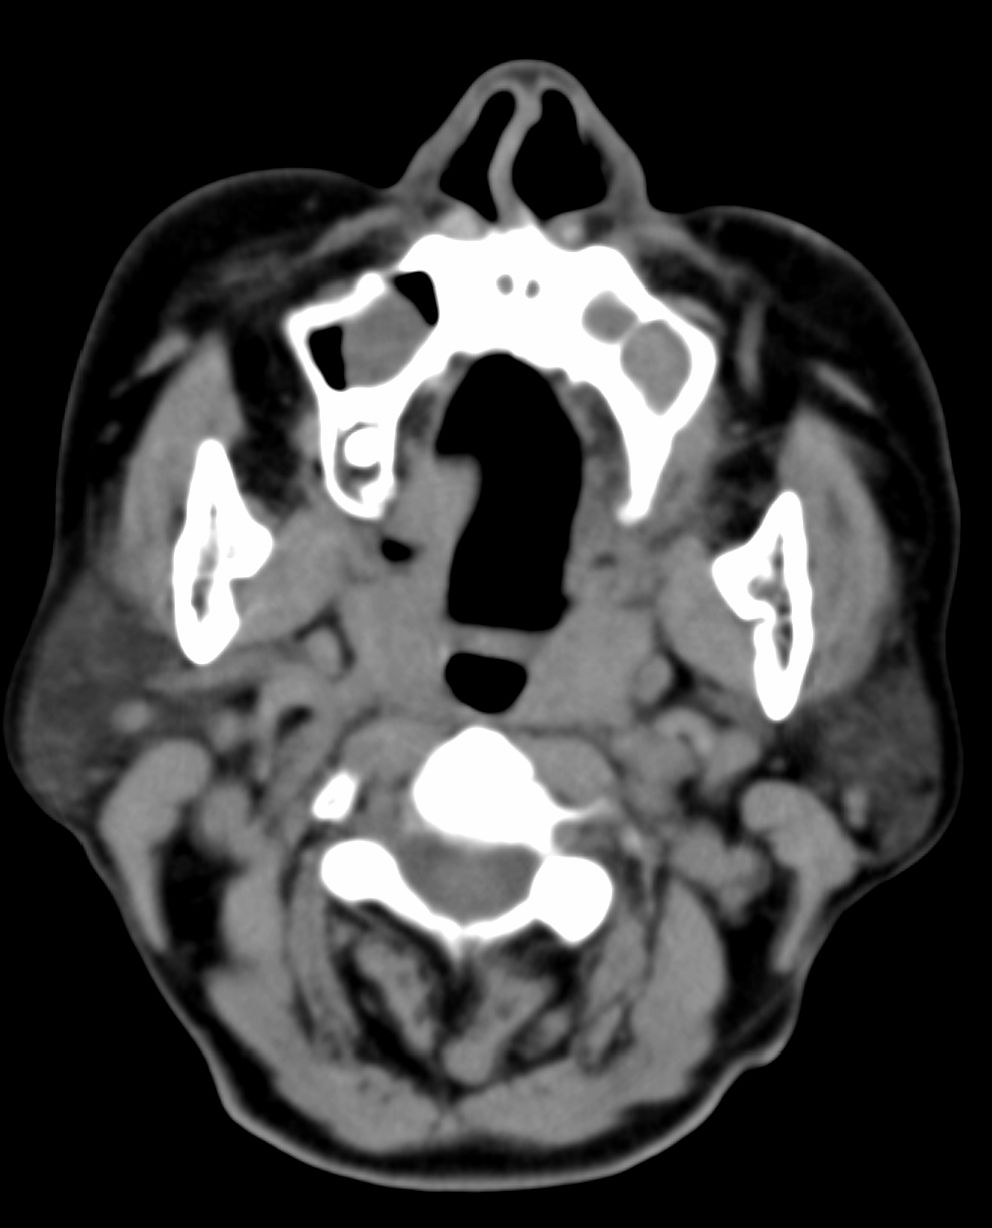

女,69岁。鼻出血2月多。(会诊病史就这样简单)鼻副窦ct检查如下:

左侧鼻腔及上颌窦见软组织块影,左侧上颌窦腔扩大,骨质吸收,右侧上颌窦见半圆形软组织密度影,鼻中隔向右侧弯曲,左侧鼻和鼻窦内翻型乳头状瘤可能性大,建议增强。

左侧上颌窦及鼻腔内见软组织密度影,其内密度不均匀,见斑片状高密度影,右侧上颌窦腔明显扩大,窦壁吸收变薄,鼻中隔右偏,右侧上颌窦见一半圆形软组织密度影,边界清楚,其内密度均匀。诊断,1、左侧鼻腔及上颌窦内翻乳头状瘤可能性大,上颌窦癌,息肉及霉菌性上颌窦炎待除外。2、右侧上颌窦粘膜下囊肿。

1)考虑左侧上颌窦内翻乳突状瘤突入左侧鼻腔。2)副鼻窦炎,右侧上颌窦黏膜下囊肿。

病理:霉菌性左侧上颌窦炎伴左侧上颌窦纤维组织增生。

窦腔密度不均匀增高,无明显钙化征象,后外侧及内侧窦壁膨胀明显,局部破坏消失,筛窦受累及,但双侧对比发现左侧窦壁骨质有硬化增白现象,这可能是支持左侧霉菌性上颌窦炎的主要依据点。